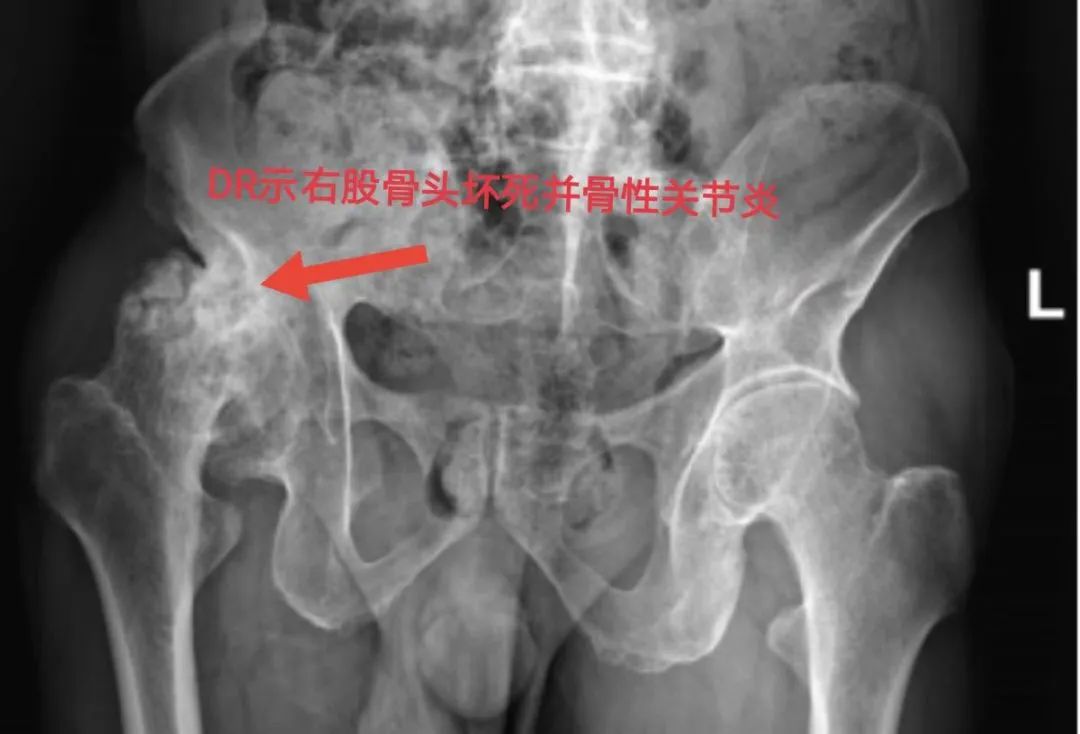

受尽病痛折磨的伍叔叔四处求医治疗,经朋友介绍,伍叔叔来到我院骨科。骨科副主任傅升培副主任医师对其进行了详细的检查。会诊后,综合考虑患者出现典型股骨头坏死三大症状:疼痛、功能受限、跛行,并结合DR、CT、MRI所见所见,明确诊断:股骨头坏死Ⅳ期。对于股骨头坏死Ⅳ期的治疗方案,目前已非常明确,就是行人工全髋关节置换术。